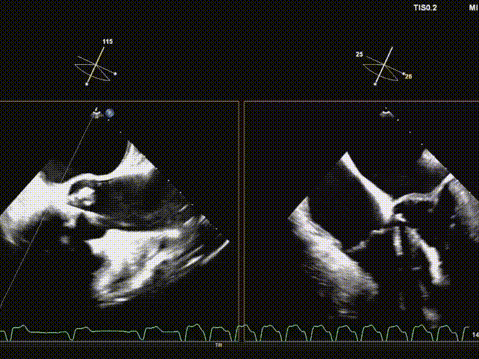

快速起搏下再次释放瓣膜至工作位,超声评估开口形态可,位置深度满意;

遂150快速起搏下完全释放瓣膜;

观察无瓣膜移动,回撤导丝后撤出系统;

术后超声评估,瓣膜位置深度满意,形态可,微量瓣周漏,最大血流速度1.53m/s,平均跨瓣压差4mmHg。